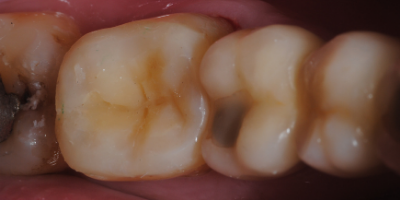

Indirect restorations are indicated for posterior teeth (premolars and molars) when the teeth have large cavities (usually resulting from caries) or simply to replace old restorations.

When the affected surface does not involve the edges, the inlays are located inside the tooth.

Onlays and overlays involve one or more edges, and some of their margins are located on the outside of the tooth.